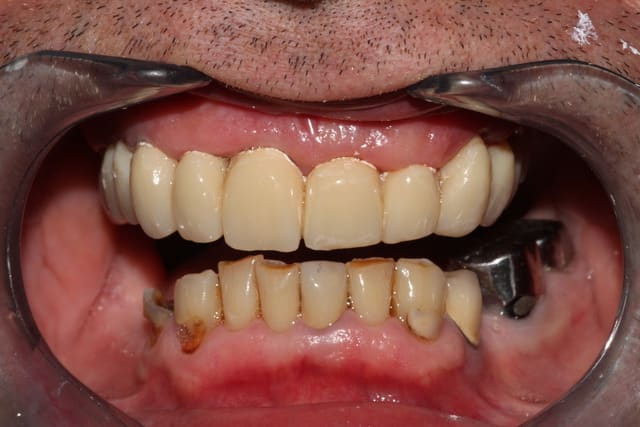

Première séance de préparation: ex 17, dépose des couronnes sans antagonistes pour se faciliter un peu le boulot de la deuxième séance, empreintes primaires.

Deuxième séance, 2h30 si mes souvenirs sont bons: préparations de tout le maxillaire, et pose du bridge pro avec une DV remontée de quelques mm. DSR manuel des poches profondes, curetage rotatif à la touati de toutes les préparations, l'accès visuel est largement simplifié.

La 12 est finalement conservée, la 24 finalement extraite.

Petit imprévu: impossible de sortir la 23, trop délabrée: je ne me sens pas de lever un lambeau lors de cette séance déjà longue, on la laisse en place pour l'instant.

Contrôle 2 jours plus tard, la nouvelle DV est bien supportée.

Les courbes occluasles ne sont pas alors idéalisées (la 36 gêne, et secteur 1 on la règlera à la plaque de fox par la suite)

Img 2165 hrc2q5 - Eugenol